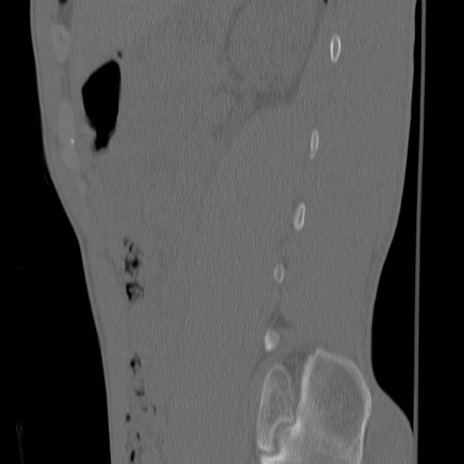

症例3 腰椎CT(矢状断像)

腰椎CT

冠状断像